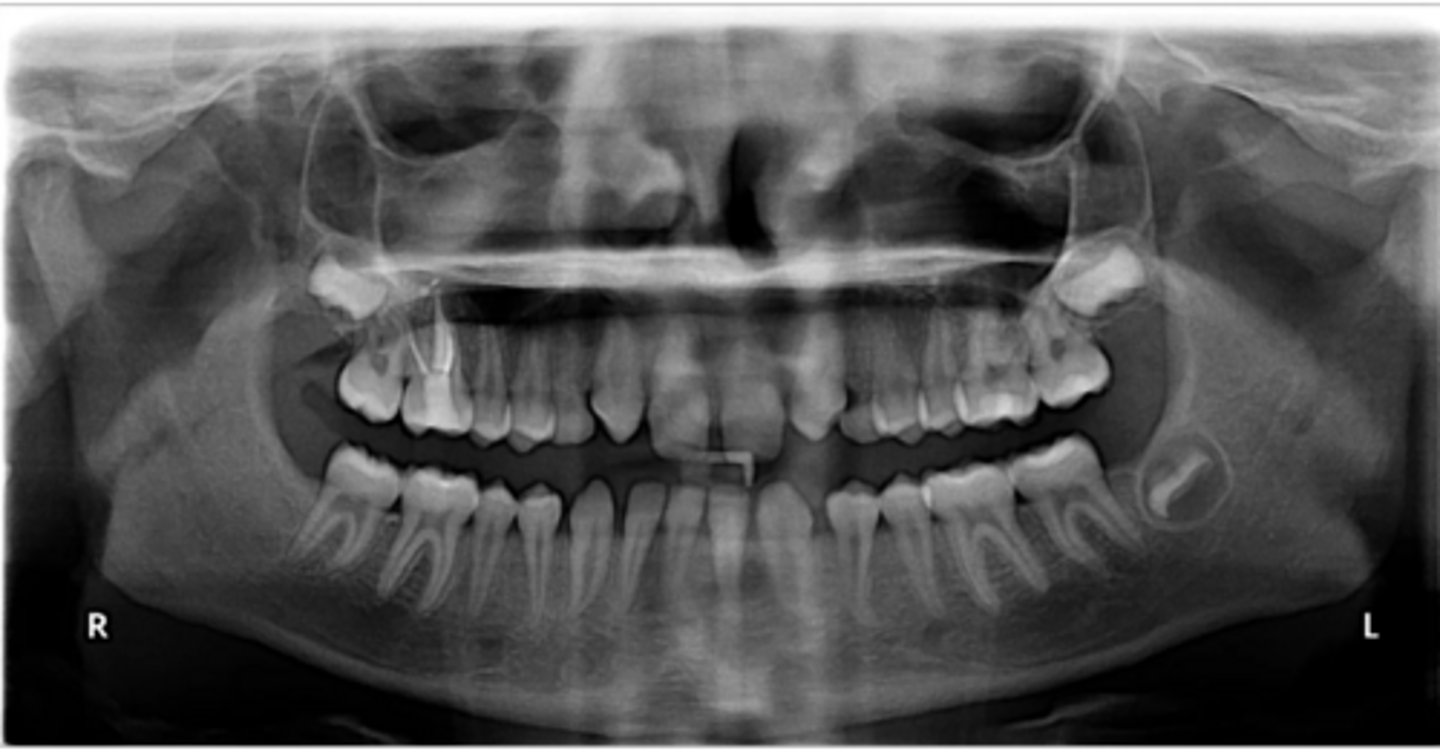

Premolar #13 (unerupted in pano) is more tilted than the opposing side (#4), which indicates an ectopic eruption pattern.

(Primary teeth w/o resorbing roots is also present)

What abnormalities/concerns do you see in this pano?

Third molars and mandibular right second premolar

Are there any congenitally missing teeth in the maxillary arch?

#29 (mandibular right second premolar)

Are there any congenitally missing teeth in the mandibular arch?

mandibular right second molar

Are there any retained primary teeth?

maxillary canines

Are there any impacted teeth?

Yes

Is there crowding?

More or less

Are the condyles symmetrical?

Maybe?

Is there any pathology?

Are there any ankylosed primary teeth?

No, just one in an odd position

Is there any ectopic eruption?

No

Are there supernumerary teeth?